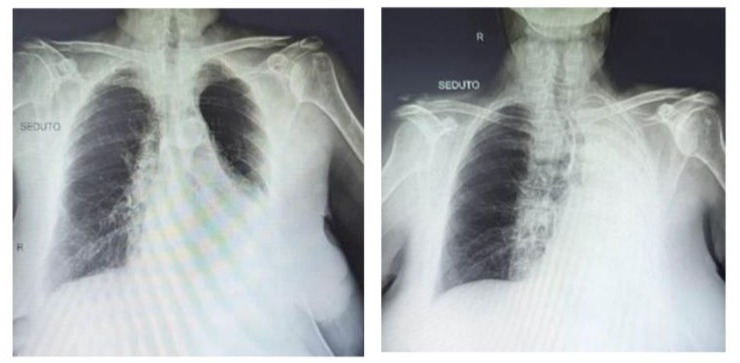

Chest X-Ray: massive pleural effusion occupying the entire left hemithorax.

During her stay in the Internal Medicine department, the patient again exhibited signs of respiratory insufficiency. Physical examination revealed absent vesicular breath sounds in the left hemithorax and the presence of moist crackles in the right hemithorax. A chest radiograph was subsequently ordered, revealing a massive pleural effusion occupying the entire left hemithorax. Based on these findings, oxygen therapy was reinitiated, and diuretic therapy was implemented, resulting in symptom improvement and gradual resolution of the effusion. Following the resolution of the infection, as confirmed by the control bronchial aspirate, the patient was transferred to a Highly Specialized Rehabilitation